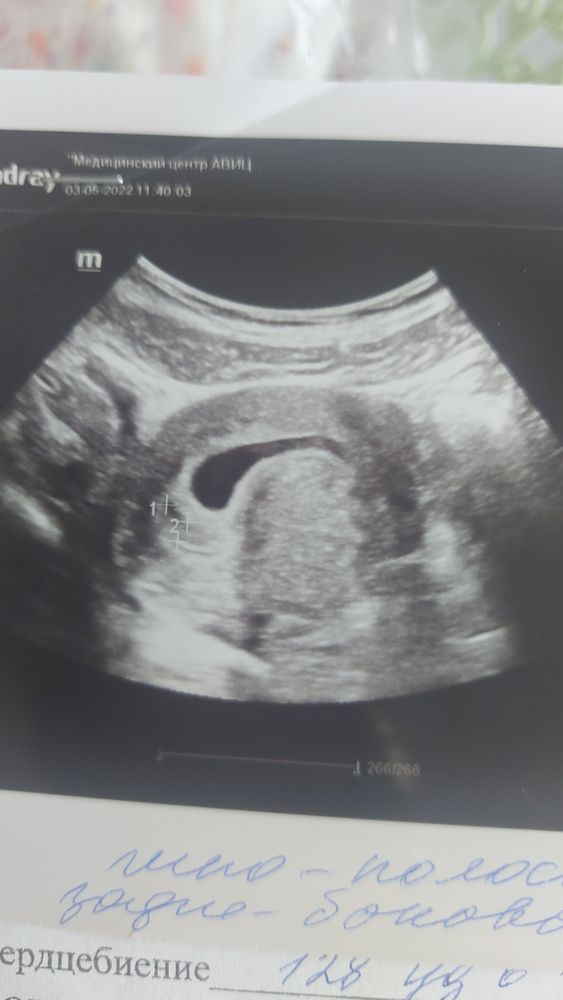

Здраствуйте была на узи. Срок 6 недель 2 дня, нашли гипо полоску размером 1.2×0.8. И не объяснили что это такое. Подскажите я правельно понимаю что это гиматома?

- так может выглядеть гематома

- такая картина в виде гипоэхогенной полоски может быть признаком «двойного децидуального кольца», характерного для беременности, и патологии в этом нет.

в любом случае - гематомы достаточно частые находки в ранних сроках, которые при малых размерах самостоятельно организуются.